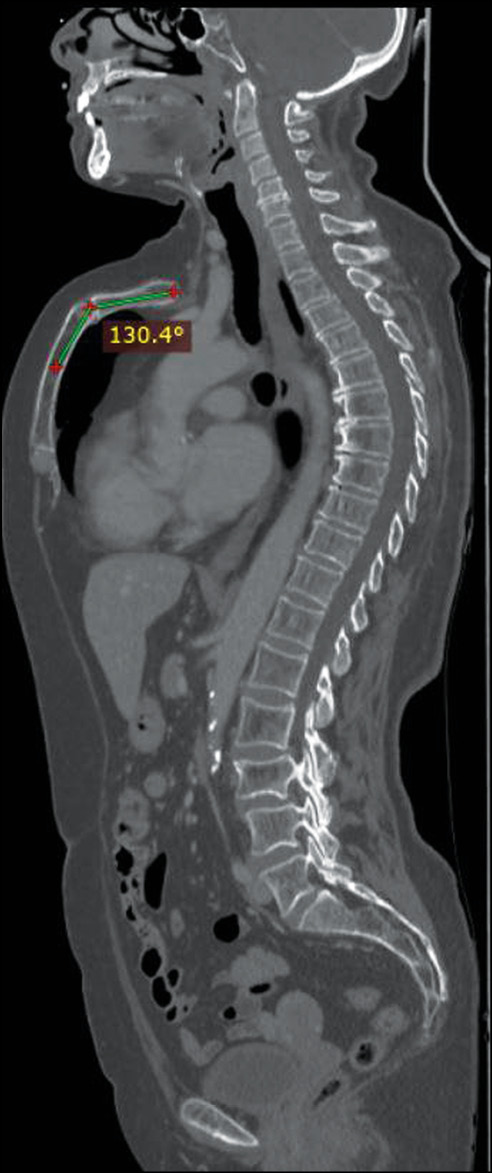

She underwent CT of the chest and abdomen with contrast enhancement, which showed the absence of metastatic lesions and any other respiratory tract disorders but revealed a chondromanubrial deformity with a dorsal-open angle of 130° and a sternum body length of 9 cm, which was not depressed in the lower third. Dorsal kyphosis was also present.

Fig 1. Sagittal whole body computed tomography scan showing an arching sternum and a chondromanubrial deformity with a dorsal-open angle of 130°.